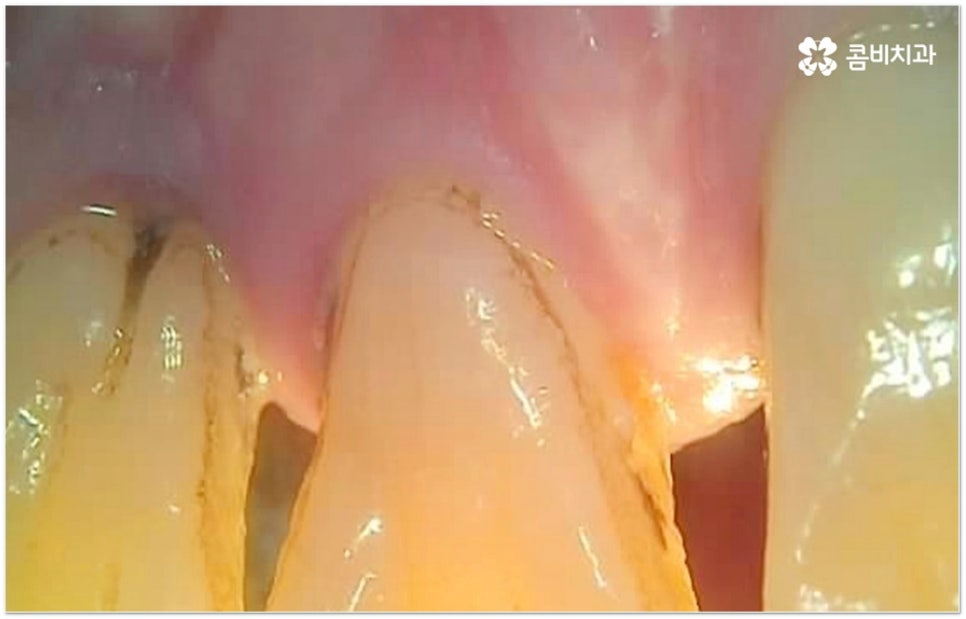

세월이 흐르면서 나이를 먹게 되면 자연스럽게 노화가 진행되기 때문에 이곳 저곳 몸의 변화가 일어날 수 있어요. 이 중 잇몸이 점차 퇴축되어 드러난 이뿌리 부분이 시리고 치아가 예전보다 온도에 민감해지는 것과 같은 구강 내부 변화는 음식을 먹을 때나 무엇을 마실 때 바로 느껴지는 변화이기 때문에 일상 생활을 하면서 유독 신경이 쓰일 수 있는데요.

만약 이전까지 칫솔질 외 별다른 관리를 해 주지 않았던 분들이라도 이렇게 약간의 불편함을 느끼시게 된 초기에 치과에 들러 검사를 받아야 할 거예요. 또한 필요하다면 상황에 맞게 적합한 치료를 진행하신 다음 앞으로 정기 검진이나 스케일링 치료 등 구강 관리를 철저하게 해 주는 계기로 삼을 필요가 있어요.

이때 누구나 겪는 과정이라는 생각에 대수롭지 않게 여기거나 무심하게 지나치는 분들도 있을 수 있는데 잇몸이 약해진 상태를 그냥 방치하게 되면 점차 악화되어 더 자주 붓고 피가 많이 나면서 퇴축도 빨라지고 (한 번 내려앉은 잇몸을 되돌리는 것은 거의 불가능합니다) 치주 질환이 심해지며 결국 치아를 상실하게 되는 결과로 이어질 수도 있기 때문에 주의하실 필요가 있어요. 잘 아시다시피 치아는 영구치 이후 탈락되면 다시 새롭게 나지 않는데 특히 성인 환자분들의 경우 치아 상실의 가장 주된 원인을 풍치에서 찾을 수 있는 만큼 잇몸 건강 관리를 잘 해 주는 것이 치아 상실의 위험에 대한 초기 대처 및 예방법으로 중요한 포인트라고 할 수 있습니다.